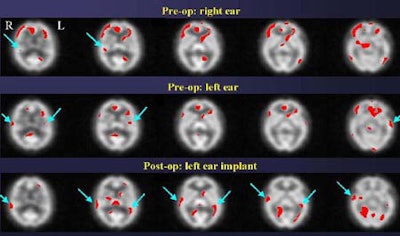

In normal subjects, the right and left-ear monoaural stimulation yielded significant bilateral activation of Brodmann areas 41, 42, 21, 22, and 38. In the monaural (right or left-ear only) studies, the highest activation levels were contralateral to the ear that received the stimulation.

"The distribution is contralateral-dominant, but bilateral once you get into the inferior slices, that is to say, contralateral-dominant in the primary auditory regions of the cortex, and bilaterally asymmetric in the association cortices for this stimulus," he said. "For left-ear presentations the same thing is true, although the contralateral dominance is not as clear for the left-ear presentation as for the right-ear presentation.... In that context we see in normal subjects significant activation of primary and association cortices in Brodmann areas 41, 22, and 38. [Area] 42 is also bilateral, but it is clearly reduced in anatomic extent on the ipsilateral side."

The implant candidates failed to activate these areas bilaterally under monaural presentations. However, bilateral activation of areas 41 and 42 were seen in the binaural tests, Devous said. He followed up with postoperative results from 3 patients.

"So this implant -- in the ear that did not show dramatic pre-op activation -- nevertheless yielded a dramatic improvement in stimulation of the auditory cortex," Devous said.

"In this patient [below], even though the two ears appear to be equally deaf based on audiological data, SPECT data shows that the brain is getting more information from the left ear than from the right ear," and the results were validated postoperatively, Devous said.